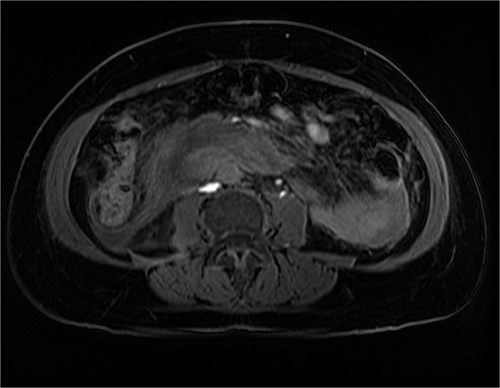

The radiologist suggested a computer tomography (CT) scan to further explore the potential causes for this fluid. The CT abdomen and pelvis revealed extensive oedema and induration surrounding the duodenum with a complex hyperdense fluid, extending from this site to the paracolic gutters and into the pelvis. While these findings are suspicious of a paraduodenal hemorrhage from a ruptured duodenal ulcer and hemoperitoneum, they were not typical for perforated duodenal ulcer or erosion into the blood vessels. Differentials were an infiltrating mass either fibrotic or of a lymphoproliferative origin. However, this could not explain the complex fluid in the abdomen (Figs 1 and 2).

CT abdomen, axial view. Hyperdense fluid centered around the duodenum and tracking into the paracolic gutters. Appearance concerning for paraduodenal hemorrhage, infiltrating mass was considered less likely.